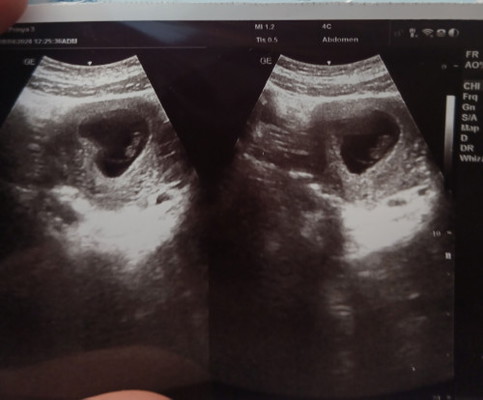

8 วีคแล้วไปอัลตร้าซาวด์ หมอบอกยังไม่เจอหัวใจน้องเต้น แถมหมอบอกให้เหน็บยา กังวลมาก ทำไงดีคะแม่ๆ